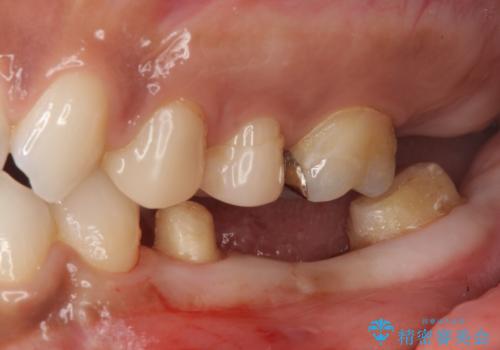

奥歯の高さがない 20代で入れ歯もインプラントも難しい ブリッジで歯を残す治療

- 他院で奥歯を抜歯してインプラントにしようといわれたとのことで来院。

虫歯を放置したため、左下奥歯の上下の歯の隙間が全くなく入れ歯もインプラントも難しい状態でした。

左下6番は残根状態だったため、やむなく抜歯を行い、⑤6⑦ブリッジとしました。